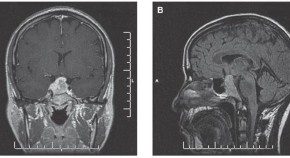

• Pituitary apoplexy, caused by infarction or hemorrhage within the pituitary gland, usually presents with headache, visual disturbance and decreased consciousness. The coincidence of these symptoms with those of more common medical emergencies might delay the diagnosis, as in the patient described here. The authors discuss diagnostic and management approaches for this potentially life-threatening syndrome.